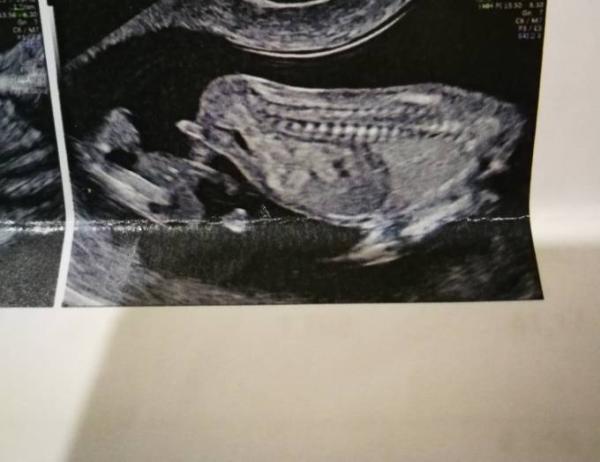

Hallo zusammen, wir waren diese Woche beim ETS und jetzt habe ich gerade das Bild gesehen, könnte das der Nun sein?

Bild zu Nub??? - Forum für April - Mamis

Mich schaut das stark nach Nub und Mädchen an

Du warst wie weit bei dem us? Wenn das echt in der 14. Woche war dann denke ich eher junge, sorry.

Denk ich ned. Meines Wissens ist das wichtigste der Winkel. Der is eindeutig Mädchen. Länge is jetzt noch unbedeutend

Die Länge ist zunächst egal. Mein Mädchen wäre demnach auch ein Junge. Der Winkel entscheidet und der NUB liegt paralell zur Wirbelsäule also ich denke es ist ein Mädchen. LG aus dem März Bus